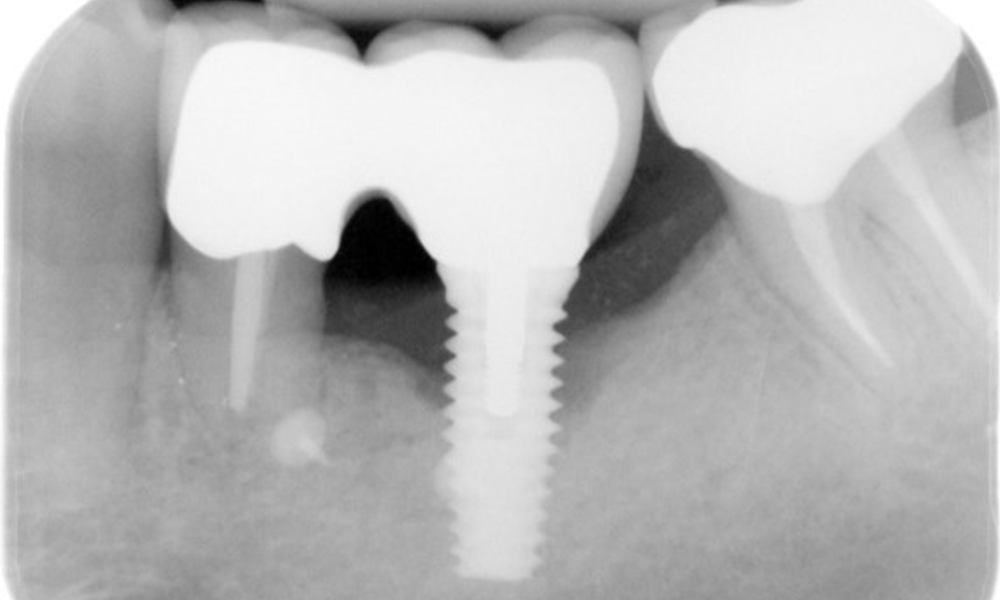

The X-ray images show the progression of bone loss.

The X-ray images show the progression of bone loss. OPG from 29.06.2020 (left) and OPG from 26.02.2024 (right).

OPG: 26/02/2024 Dental X-ray: 18/01/2024

The X-ray images show the progression of bone loss in the area of the implant in region 36: dental film from 11.02.2021 (left) and dental film from 18.01.2024 (right).